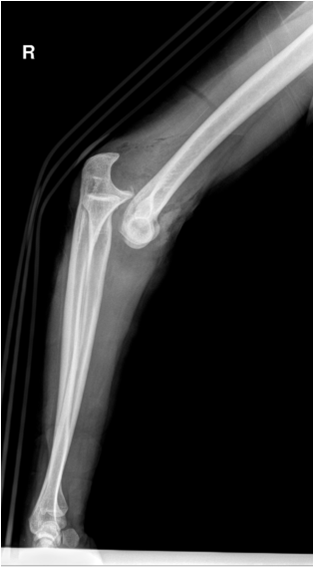

17.2.1.1. Stress films:

Joint relationships can frequently be evaluated better with the aid of stress films. Stress may be applied either by weight bearing (evaluation of the acromioclavicular joint) or by external stress applied to alter the at-rest relationship (evaluation of ankle ligaments). Stress films are used to test joint stability in suspected ligament injury. Images are taken under defined conditions with weight or pressure applied. Subluxation or joint space widening indicates partial or complete rupture of the ligaments tested. Before ordering stress images a set of conventional images in mandatory to exclude fracture.

Fig. 4. Stress test of acromiclavicular joint instability. The patient is holding 10 kg weight in each hand. Note the step in the right acromiclavicular joint indicating injury to the ACG capsule and the coracoclavicular ligament.